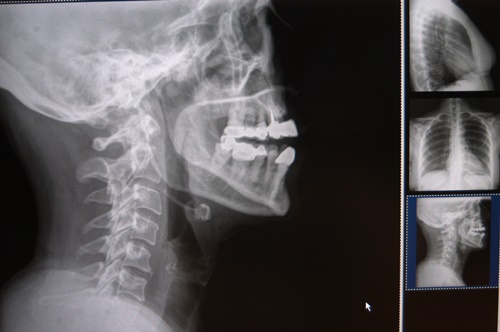

Explicó que la columna cervical se sitúa en el cuello, su función es contener y proteger la médula espinal, soportar el cráneo y permitir los diversos movimientos de la cabeza: rotarla de un lado al otro, inclinarla hacia adelante o atrás.